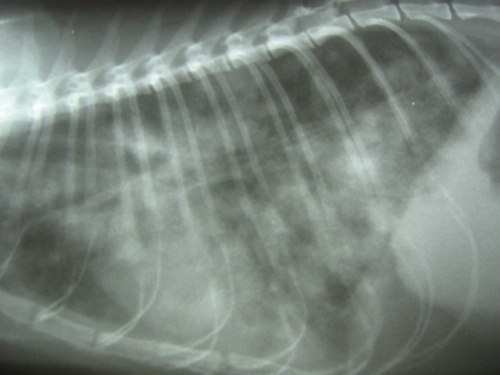

Lorsque le diagnostic de tumeur est établi, il faut réaliser un bilan d'extension : c'est l'ensemble des examens qui permettent de voir si la tumeur est opérable ou si elle a déjà commencer à s'étendre à d'autres organes (envahissement local, régional ou métastases à distance). Le bilan d'extension passe par l'imagerie : la radiographie ou l'échographie permettent de visualiser des nodules déjà assez gros, alors que le scanner met en évidence des lésions de l'ordre du millimètre. L'endoscopie ou la cœlioscopie permettent également de faire des biopsies de lésions.